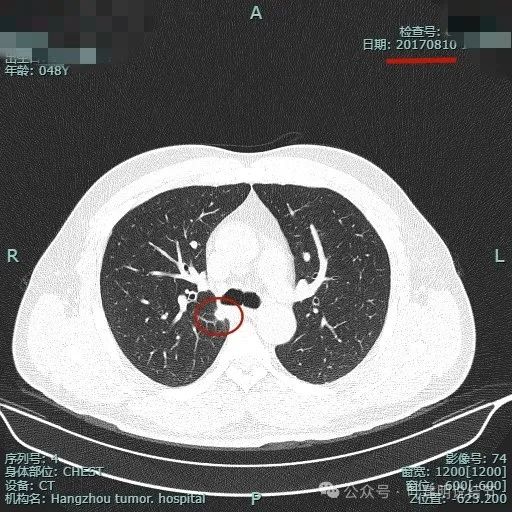

先看2017年初发现时的:

2017年8月时此灶就有,而且也是实性的,大小相差不多,最大层面现在的似乎略有饱满点。